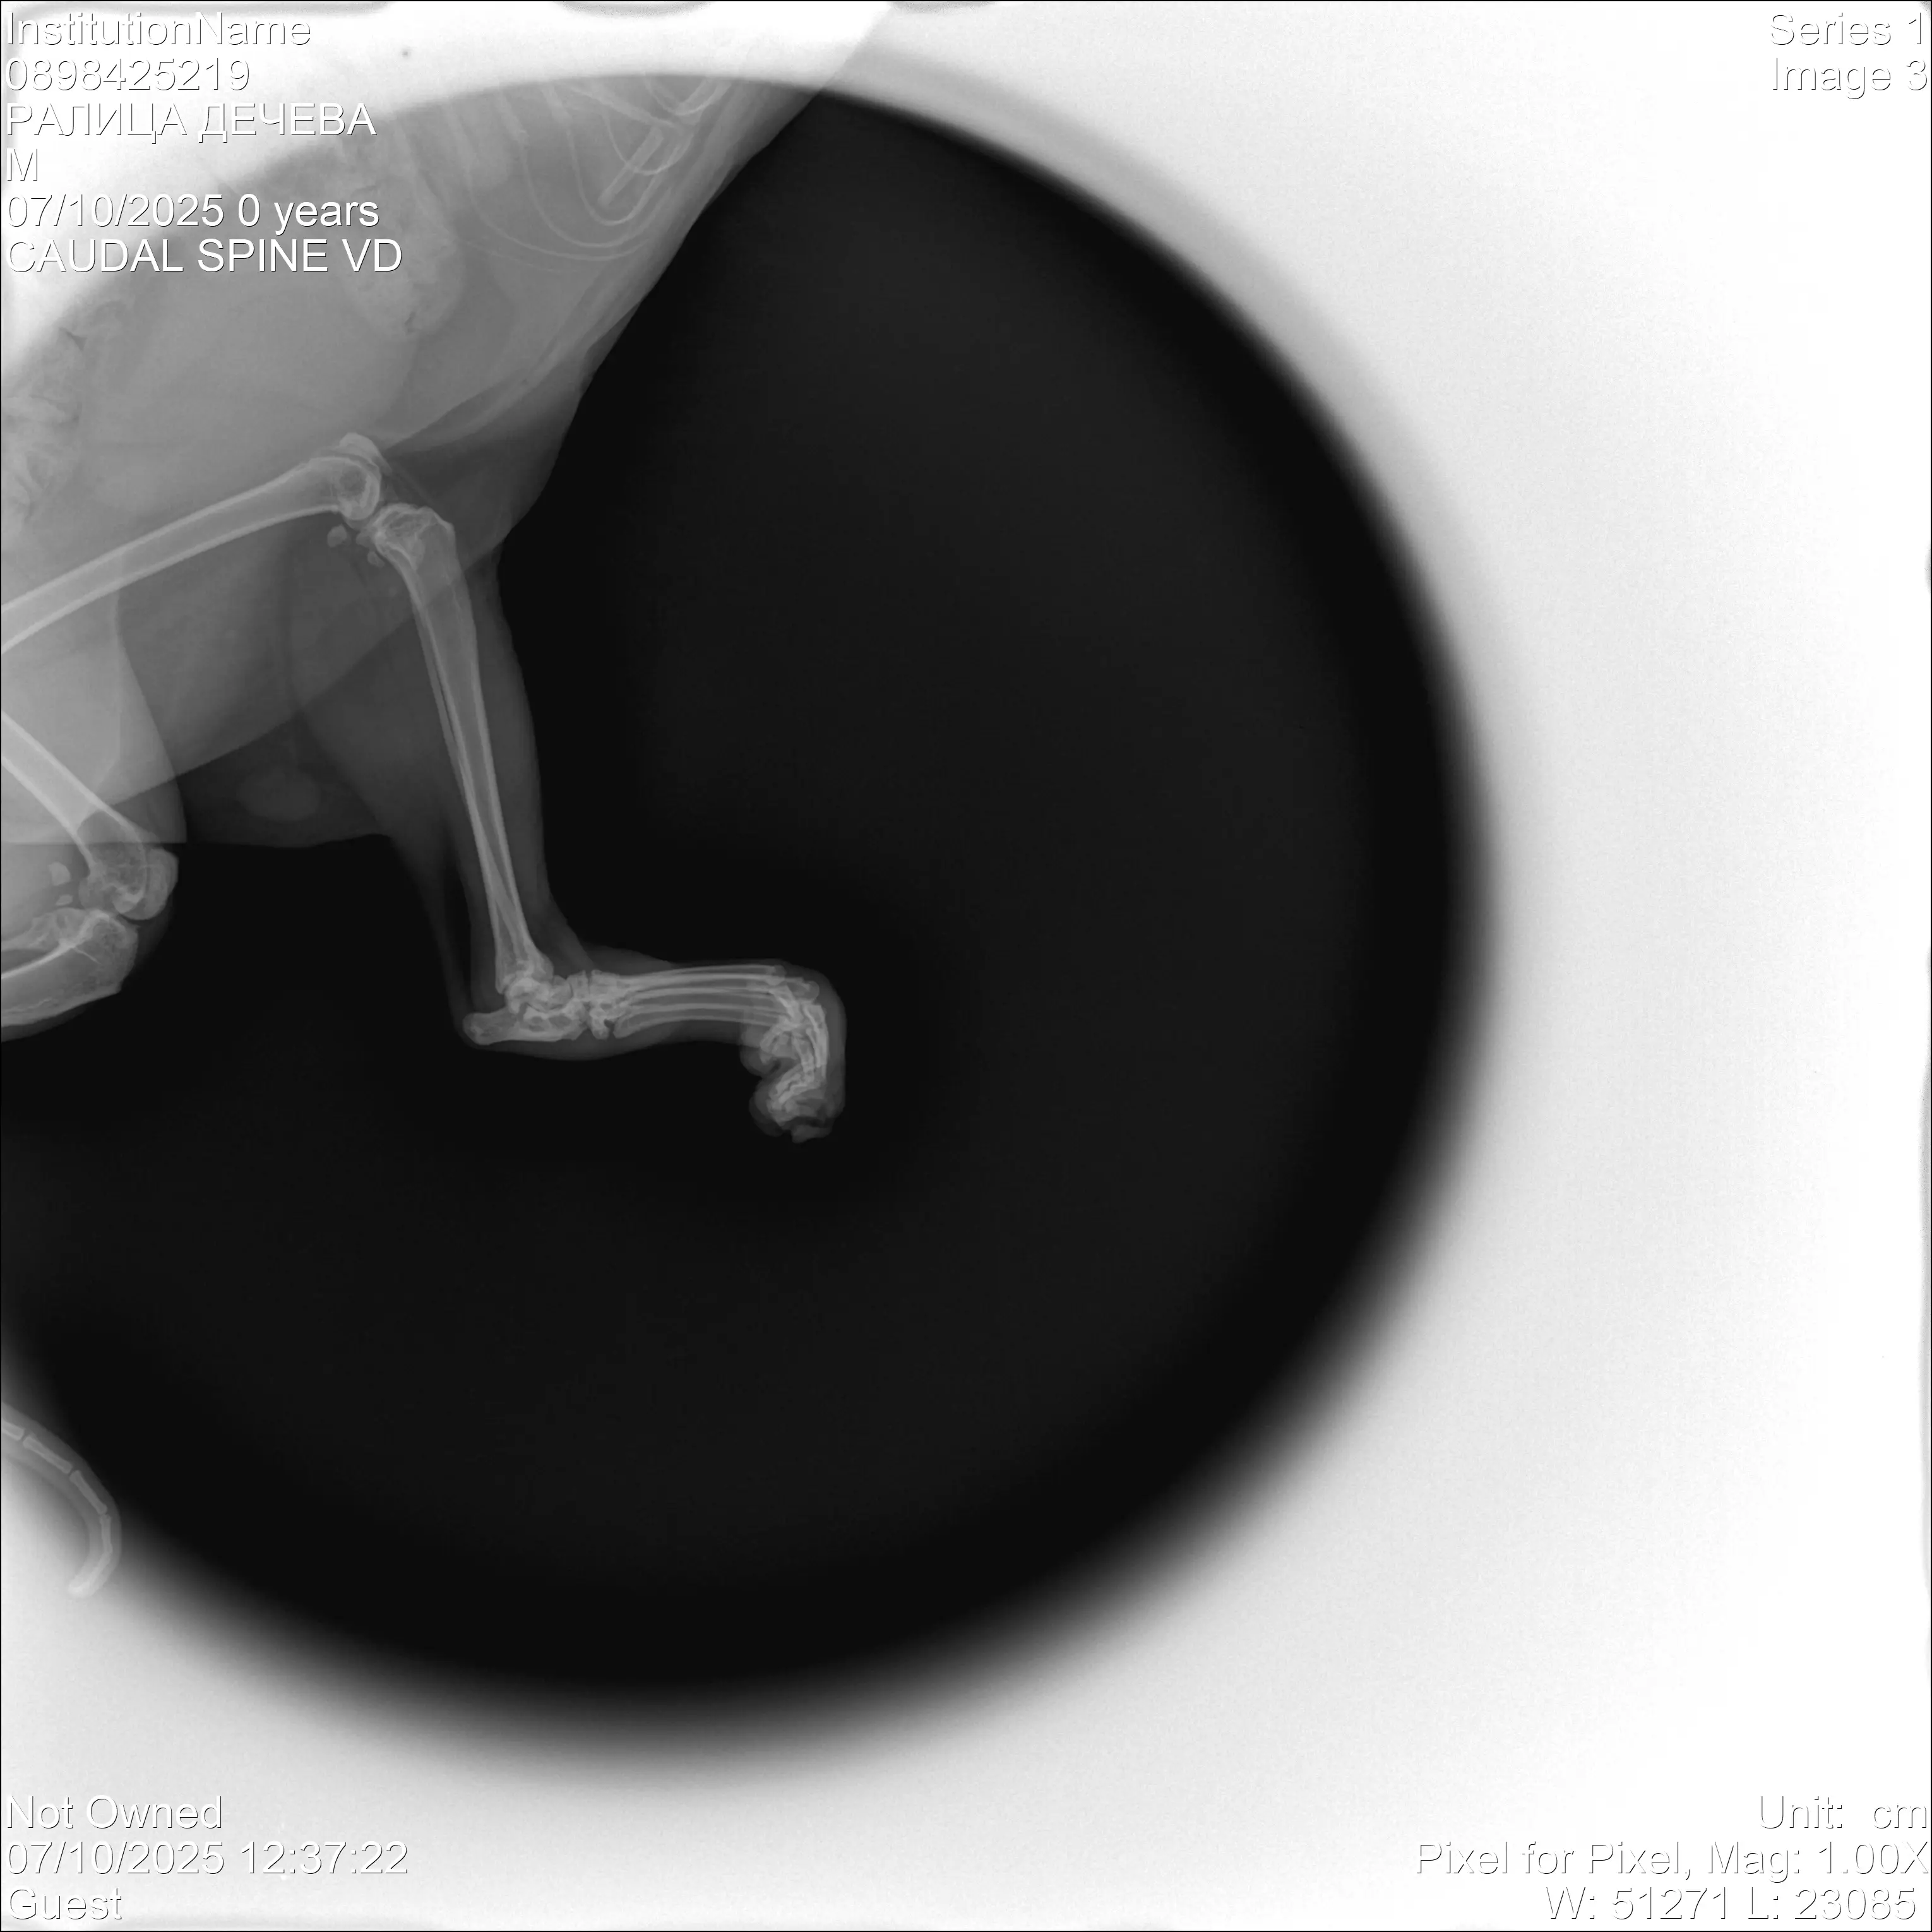

Това е Тигърка. Тя е бездомниче, което започанах да храня преди 2 години. Миналата година изчезна за две седмици и като се върна, разбрах че я е сполетяло нещо лошо, влачеше си и двете крачета. След преглед и консултация с ветеринар, направихме рентгенова снимка и се установи,че е със счупен гръбнак. Прогнозата за Тигърка беше много отчайваща, препоръчаха ми евтаназия, понеже увреждането на гръбначният стълб беше много сериозно и имаше вероятност да не може да се справя сама с физиологичните си нужди. Аз не можах да взема решение за евтаназия веднага и реших да опитаме с лечение - нивалин, милгама и др., както и рехабилитация. Бавно и трудно, но резултат имаше - Тигърка се обслужва сама, единият крайник се възстанови, но другият - няма дълбока чувствителност. Възможността за нея, за да има един по-добър и пълноценен живот е да се ампутира частично крачето и да се направи протеза с титаниева шина.